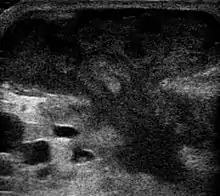

Метод выбора лечения абсцесса брюшной полости — чрескожное дренирование или пункция под контролем УЗИ.

- UOTW #66 — Ultrasound of the Week. Ultrasound of the Week (7 января 2016). Дата обращения: 27 мая 2017. Архивировано 2 ноября 2016 года.